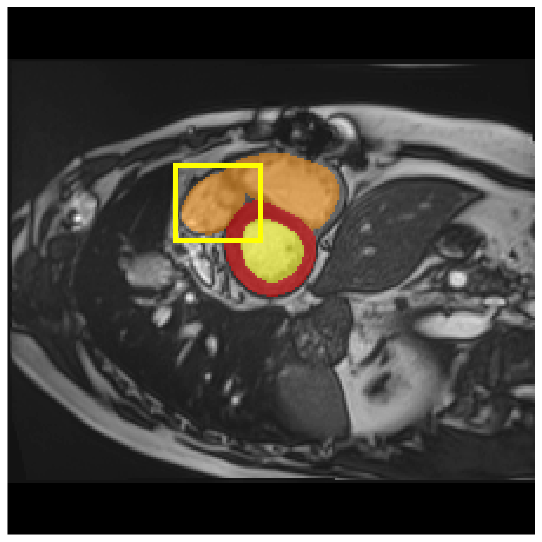

4.3.2 Visual Comparisons

Visualization of our method on the Synapse and ACDC datasets is shown in Fig. 3(a) and Fig. 3(b). For the Synapse dataset illustrated in Fig. 3(a), FCT failed to accurately segment SM and GB, while MERIT achieved precise segmentation of SM but struggled with GB. In contrast, our method achieved accurate segmentation of both SM and GB. Regarding the ACDC dataset shown in Fig. 3(b), while previous methods achieve comparable segmentation of the Myo and LV to the GT, they exhibit noticeable errors on the RV, including invasion into adjacent organs and misrecognition. On the other hand, our method accurately segments across all three structures Myo, LV, and RV, performing as precisely as the GT. We demonstrate the superiority of our method quantitatively and qualitatively.